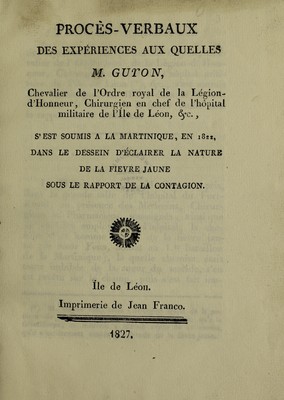

Procès-verbaux des expériences aux quelles M. Guyon ... s'est soumis à la Martinique, en 1822 : dans le dessein d'éclairer la nature de la fièvre jaune sous le rapport de la contagion / [Jean Louis Geneviève Guyon].

- Jean Louis Geneviève Guyon

- Date:

- 1827

Credit: Procès-verbaux des expériences aux quelles M. Guyon ... s'est soumis à la Martinique, en 1822 : dans le dessein d'éclairer la nature de la fièvre jaune sous le rapport de la contagion / [Jean Louis Geneviève Guyon]. Source: Wellcome Collection.